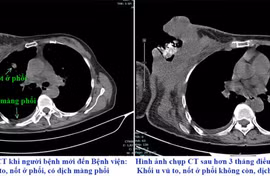

Với những trường hợp mắc hội chứng thận hư nhưng tự ý bỏ thuốc như người bệnh sẽ có nguy cơ mắc những biến chứng nguy hiểm như tràn dịch màng, tắc mạch do huyết khối, suy thận…